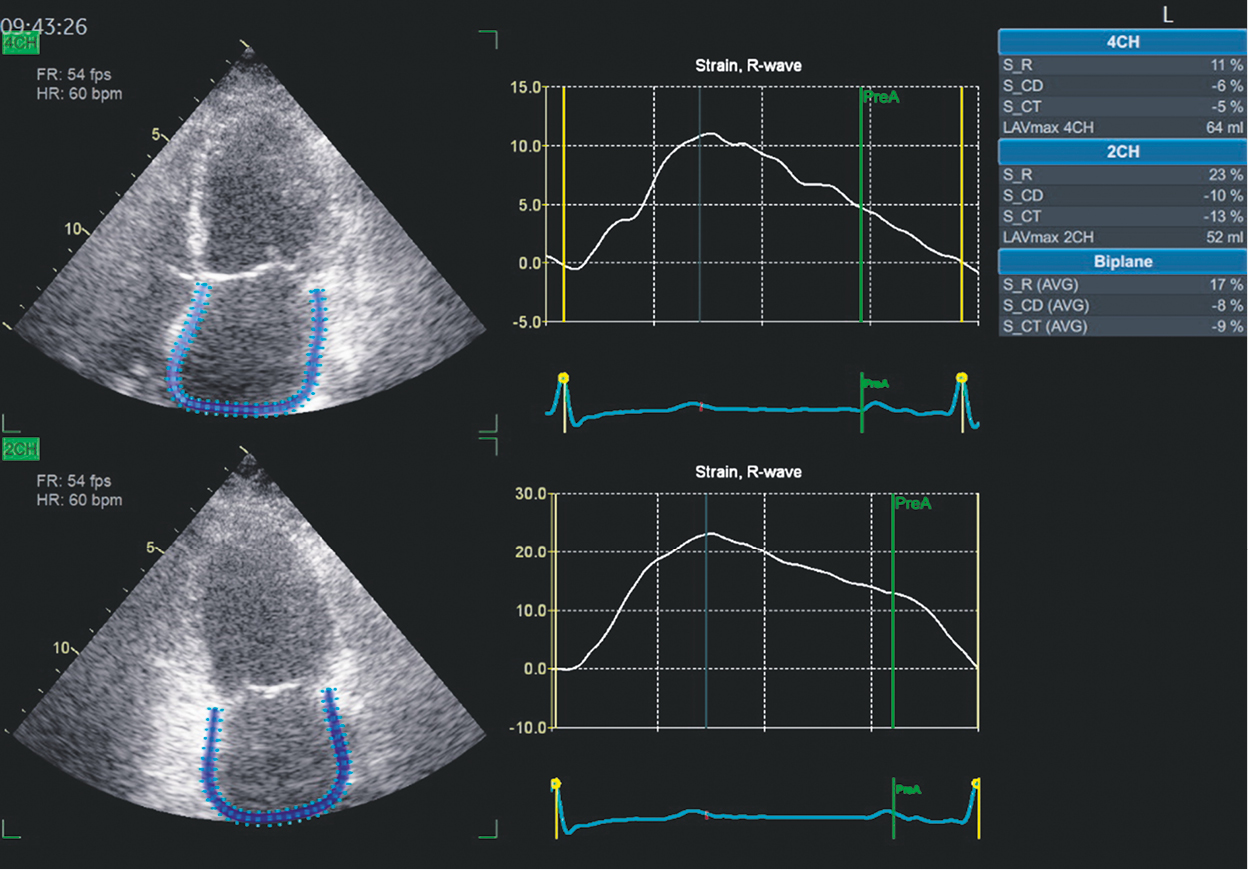

In addition to LV diastolic function improvement, the LA volume tended to decrease (Fig. 4). Indices of LA function have improved. Consequently, the proportion of LA myocardial strain increased from 13% to 17% during the reservoir phase, from 5% to 8% during the conduit phase, and from 8% to 9% during the contractile phase. The dynamics of the indices are presented in Table 3.

Fig. 4. Assessment of left atrial function over time in February 2024 in 2D-Strain mode. Explanation in the text

In consideration of the notable LA dilatation, LA function was evaluated in the longitudinal strain mode (2D strain) (Fig. 3). As in the case of longitudinal LV myocardial strain, LA myocardial strain parameters were abnormal. The deformation index during the reservoir phase was equal to 13% (with a mean normal value of 39%, 95% confidence interval [CI] 38%–41%). During the conduit phase, it was 5% (with a mean normal value of 23%, 95% CI 21%–25%), whereas during the contractile phase, it was 8% (with a mean normal value of 17%, 95% CI 16%–19%) [6]. Notably, the strain indices during the conduit and contractile phases were negative, as the LA myocardium shortens during these phases. For the convenient comparison of indices, it is customary to discard the minus sign. In our patient, the LA function during all three phases was significantly impaired. Because the assessment of LA myocardial strain was performed for the first time, it was not possible to ascertain the extent to which LA function had been disturbed previously.

Fig. 3. Assessment of left atrial function in 2022 in 2D-Strain mode. Explanation in the text